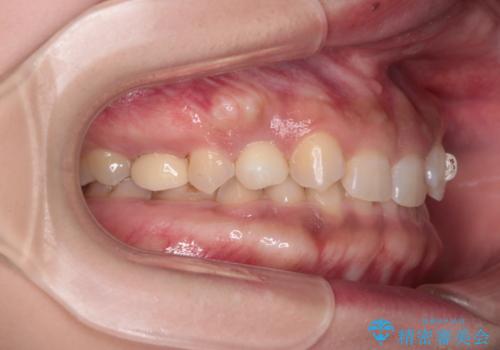

- 後続永久歯が欠損した患者様です。

矯正治療にて歯並びを改善したのち、インプラントにて咬合回復を行う治療計画としました。

捻転が強い部分だけはワイヤーの部分矯正で対応しております。